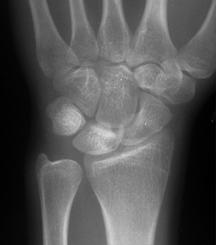

Stage III 부터는 주상골도 영향을 받기 시작하며 회전을 하거나(IIIA, cortical ring 관찰가능), carpal height 가 줄어드는 것을 확인할 수 있습니다. (IIIB), IIIA 까지는 II와 치료를 거의 동일하게 하지만, IIIB 부터는 Proximal row carpectomy 나 STT, SC fusion 등을 시행해 볼 수 있습니다.

단계별로 보면 다음과 같습니다.